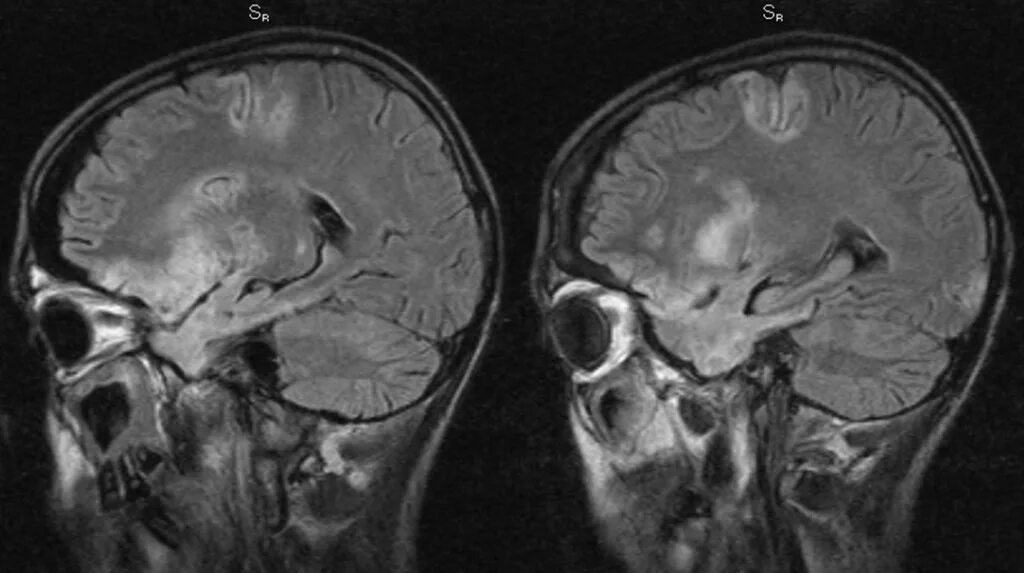

Диффузные повреждения